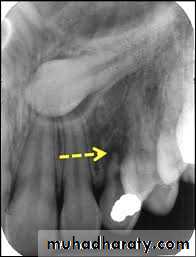

The periapical radiograph provide a detailed picture of the tooth and its surroundings and is helpful for demonstrating the degree of root formation of the canine , apical curvature , the existence of any root resorption affecting the adjacent lateral incisor and the presence of an associated cyst .Mosul university- College of dentistry-oral & maxillofacial surgery department

The relative radiopacity of the crown of the impacted canine may assist in the determination of the tooth position (the more radiopaque lie palataly )

Parallax method in this technique a periapical radiograph of the area is taken and the x ray tube is then moved in either mesial or distal direction before a second periapical film is taken .the two radiograph is then compared and if the impacted tooth seen to move in the same direction as the x ray tube it is lying palataly , whilst if it moves in the opposite direction it is lying labially.